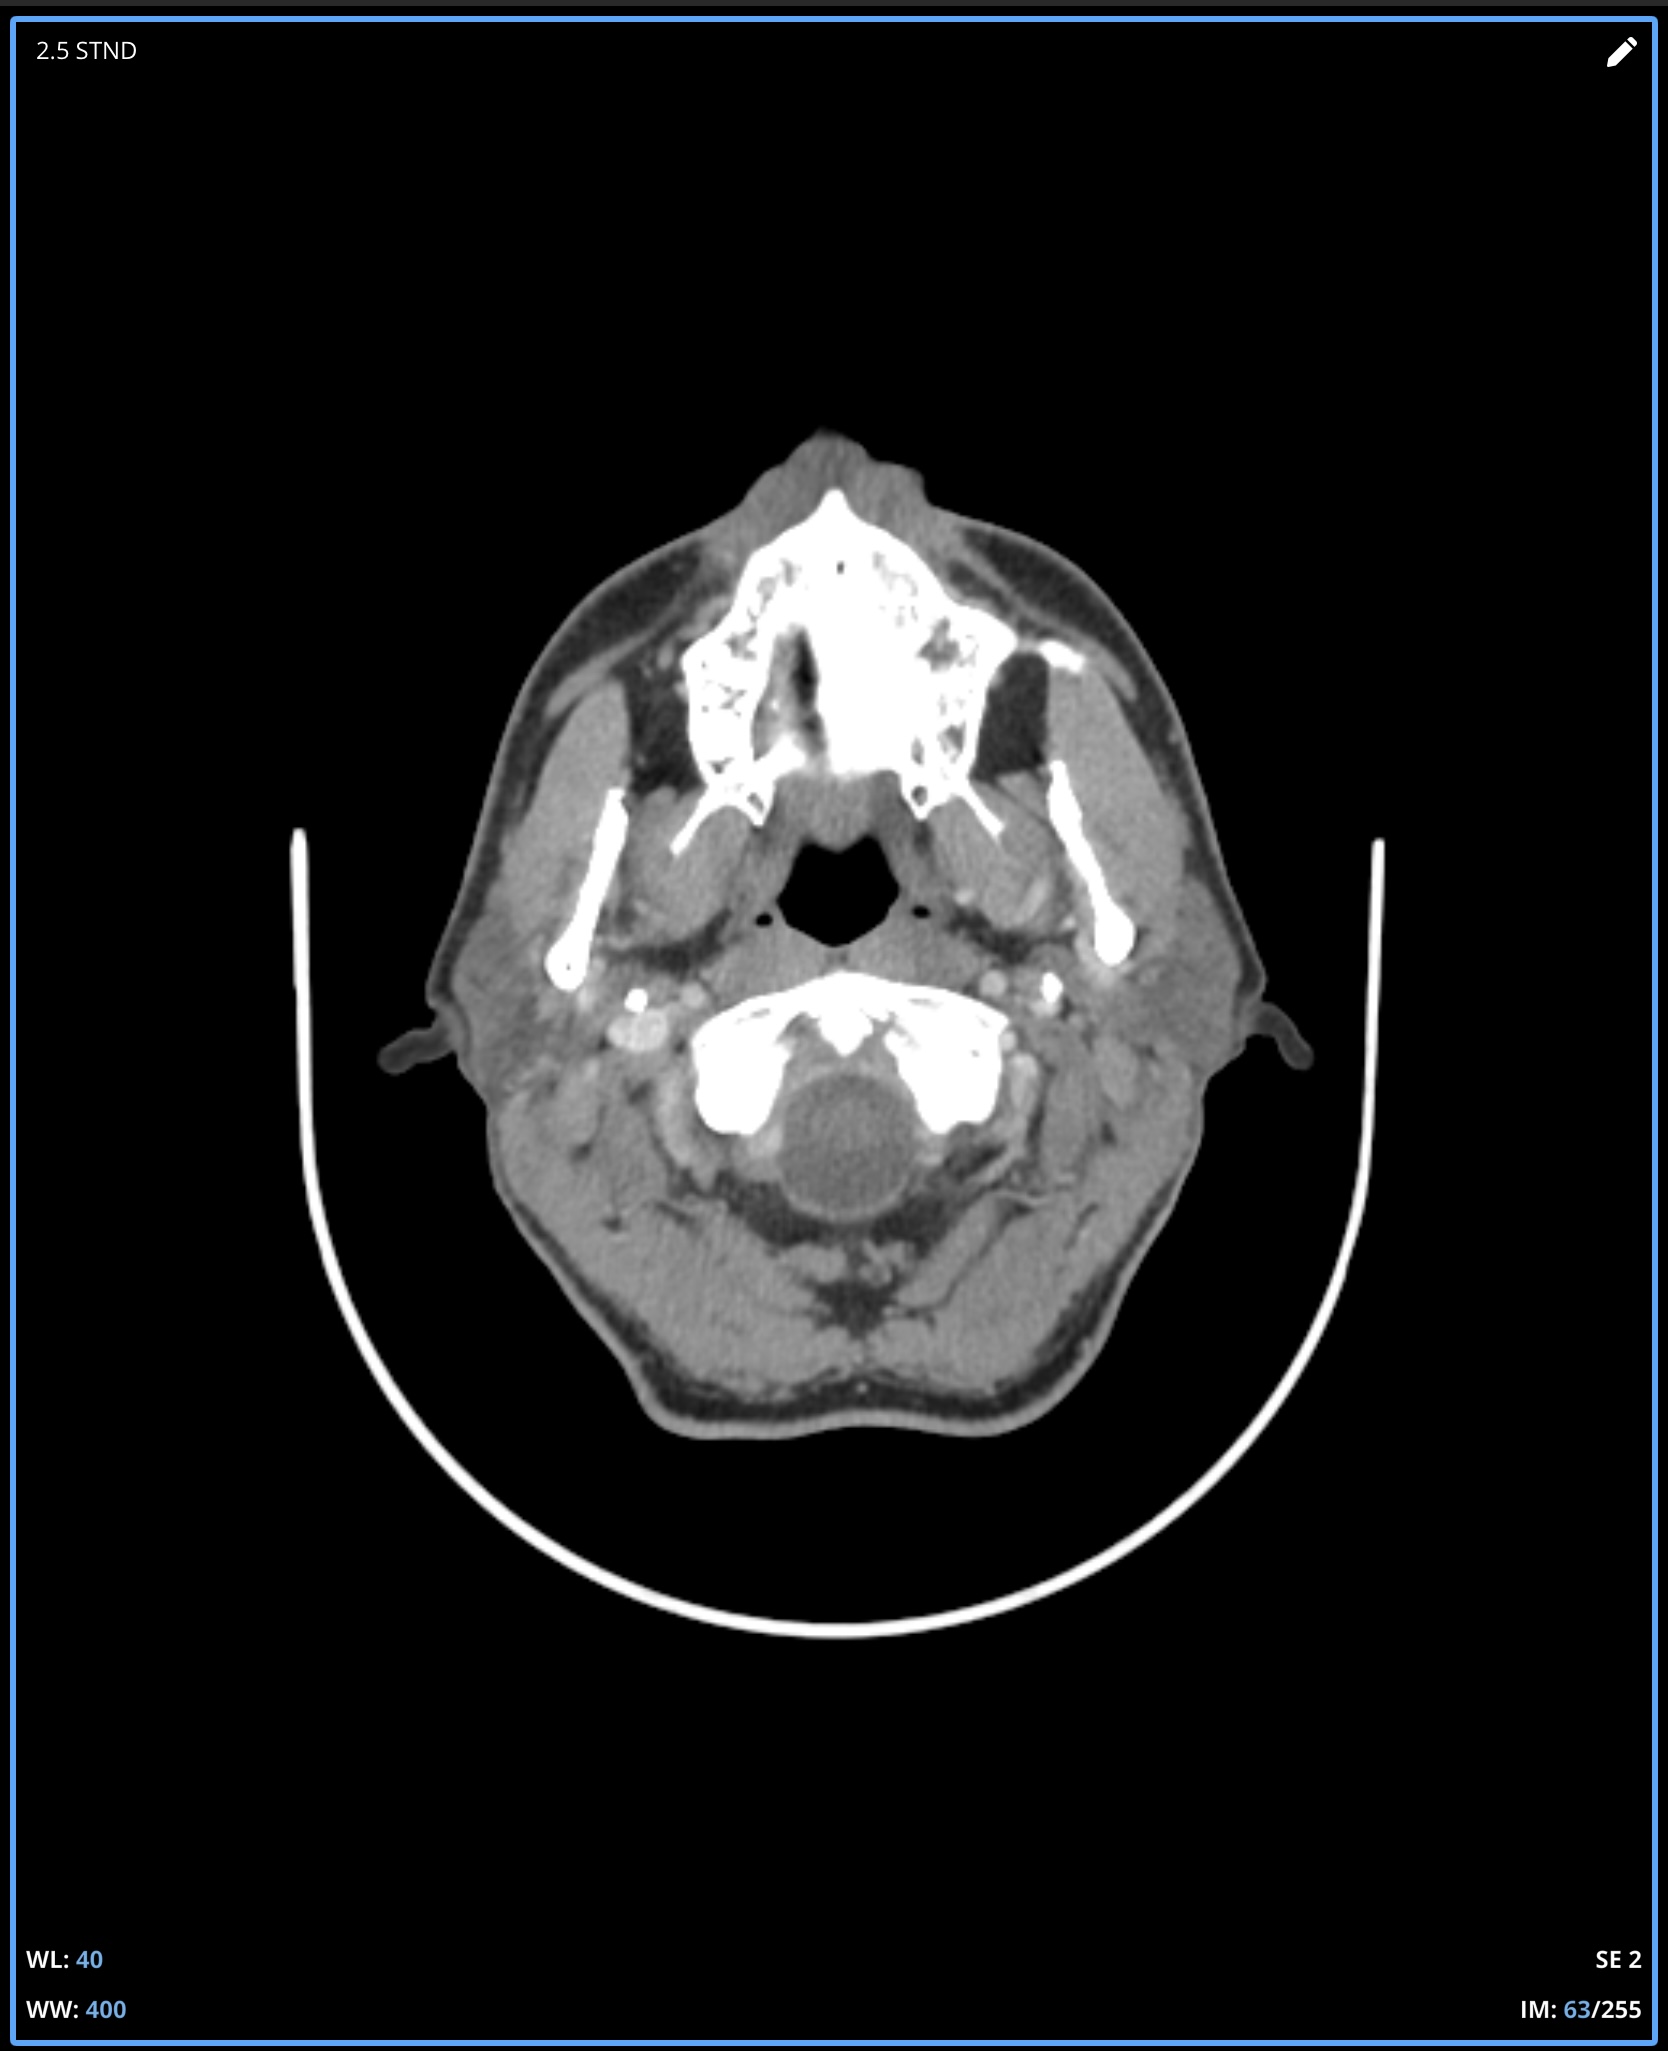

I’m not good at tech so can’t do labels or arrows for your imaging, but on the first two images, there’s clear compression of the IJV between the styloid process & the C1 process. In the first one, it’s not clear whether it’s just the imaging or whether there’s also narrowing of the IJV further down- it disappears so that could be compression but can’t see clearly, if it was compressed there it would indicate TOS which might explain some of your arm symptoms…

In the other two CT images, you can see the styloids really clearly- they’re quite elongated, pretty thick right at the top, and both sides look close to the C1 processes, which is a common place for the IJVs to get compressed.

Where I am in Canada and the healthcare system is slow, I travelled to a different province in November for an updated CT. The report did note a pretty severely squished left jugular between C1 and the styloid and some compression on the right side as well so at least it is acknowledged on a report now. It sure looks like C1 is causing a problem even moreso than the styloid but I am not in a position to figure this out. I can’t help but wonder if I was born this way and it’s actually not the problem at all. Anyway, I would appreciate any feedback whatsoever on these new images….is a C1 shave a must do? I hope this isn’t too many images to post, I was trying to show the full picture of how the compression looks. It is very difficult to pick out the left jugular because it becomes so small:

It’s clear that your right IJV is dominant based on its size vs the left one. I’ve annotated a couple of your 3D images to show what I see & will comment below them. Scrolling through your axial images, it’s obvious you have significant bilateral IJV compression.

Your left IJV appears to be predominantly compressed by C1 as you suggested, however, there is secondary compression lower down which appears to be caused by your ICA, however, it could be coming from your SCM which could be impacting both the left IJV & ICA.

Your right IJV appears to have a small clot at the level of the C1 compression, although this could simply be C1 pressing from the back side. I’d sure talk to a doctor about the way that looks though.

Additionally, it looks like your right IJV is twisted part way down which may be causing some compression at that level. I haven’t seen this before. It may just be an illusion in the imaging & not an actual twist.